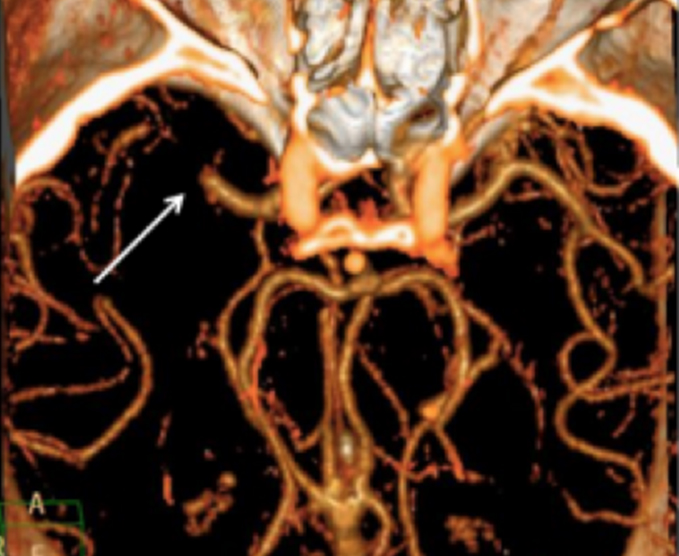

Angiotomografías

La angiografía por TC (ATC) combina una tomografía computarizada con la inyección de una tintura de contraste. TC significa tomografía computarizada. Esta técnica es capaz de crear imágenes de los vasos sanguíneos para detección de anomalías.

- Arterias cerebrales

- Arterias de cuello